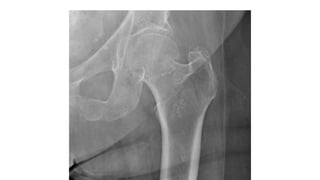

This document discusses femoral fractures, categorized by their location and severity, with classifications such as Garden classification. It outlines the types of fractures, including valgus impacted, non-displaced, partially displaced, and fully displaced, along with their surgical treatment options. Additionally, it briefly describes distal femur fractures, which occur just above the knee joint.